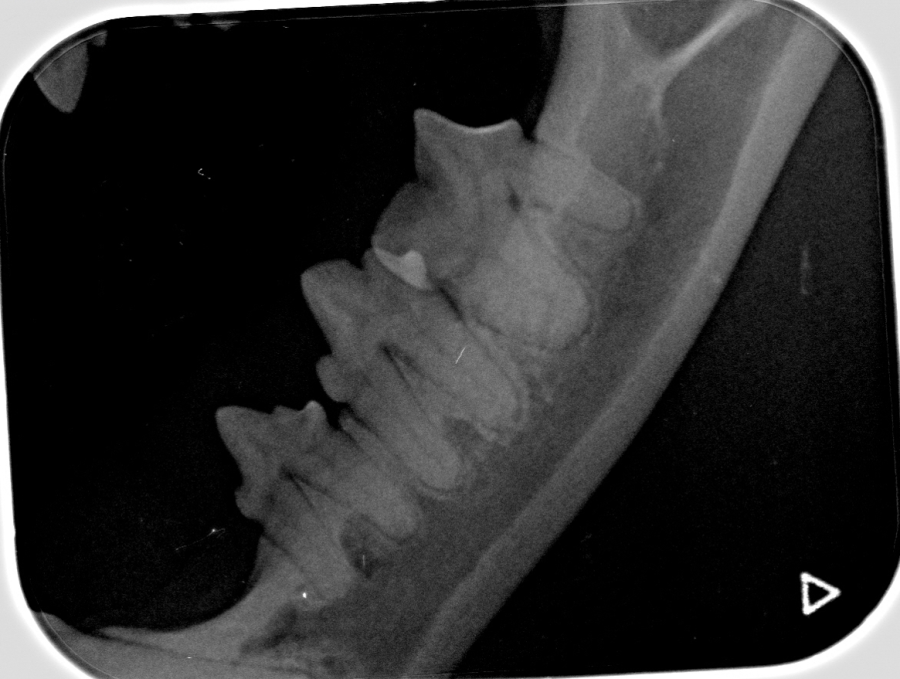

Dental Röntgen

Um bei einer Zahnbehandlung auch den Status der Zahnwurzeln und des Kiefers beurteilen zu können, benötigt man ein Detal Röntgen, denn viele Probleme schlummern unter der Oberfläche (siehe Zahnbehandlung).